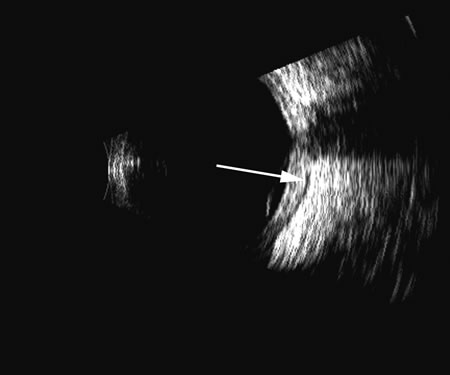

Fig. 18. A foreign body localized in the iris is easily imaged with high frequency. Characteristic trailing multiple echoes always point to the location of the body itself (arrow).

Vitreous foreign bodies are typically metal or glass objects, or intraocular lens implants. The ultrasound examination, with its better spatial resolution, is best performed following radiographic or computed tomography examinations in order to identify the location and number of foreign bodies. Ultrasonography is used to relate the position of a foreign body to the retina and lens and identify coexisting structural changes, such as retinal detachment. Metal and glass “absorb” or, more correctly, deflect sound, so that an anechoic area appears posterior to the foreign body. This area can act as an acoustic “pointer” to the foreign body (Fig. 18). A-scan or gray scale on B-scan shows a highly reflective surface of the foreign body. BBs and shotgun pellets often create a “ringing” artifact that can also act as a pointer leading to the foreign body.19 The foreign body can be easily demonstrated by lowering the gain; the foreign body remains, whereas other, less reflective tissue planes fade away due to a lower difference in acoustic impedance between tissues than metallic or glass foreign bodies. Most foreign materials have a higher density than the vitreous, and sound that passes through the foreign body may appear to move the succeeding surface forward because of the faster sound transit.